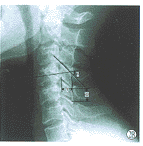

楼主所指的枢椎棘突密度减低区属正常表现,你可能多拿几个颈椎侧位片看看。

下面是我刚从网上下载的几张颈椎图片。